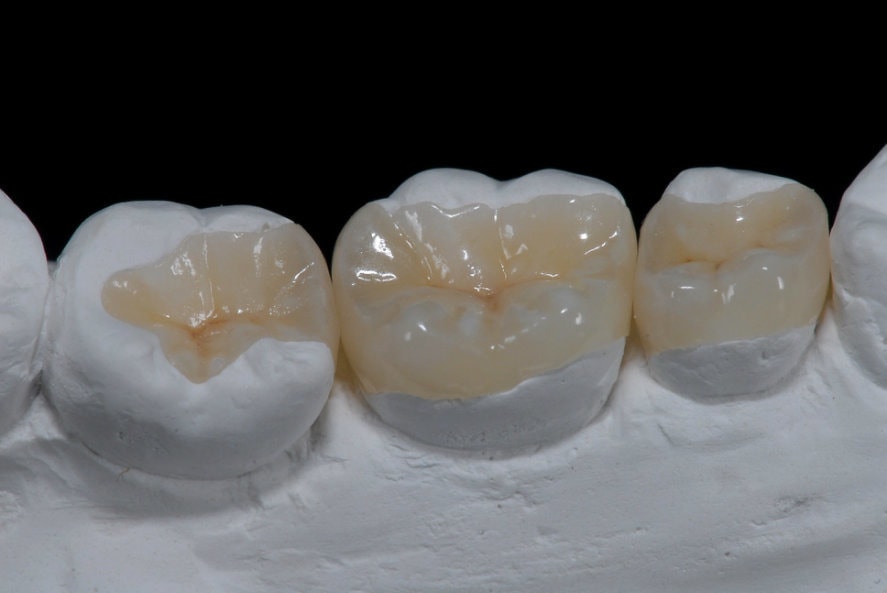

Inlay, onlay, overlay

Sérült, destruált fogak ellátására alkalmazott, az őrlő, kisőrlő fogakra ragasztott, fogtechnikus által készített, fogpótlásnak nem minősülő fogtömés, ismertebb nevén betét. Ha a fog kifúrása után a megmaradt egészséges foganyag már túl kevés ahhoz, hogy egyszerű tömést készítsünk, de még túl sok, hogy a fogat egy koronához teljesen lecsiszoljuk, úgy a betét az ideális választás. Kiterjedése szerinte inlayàonlayàoverlayről (növekvő sorrend) beszélhetünk. Nagyon sokszor használjuk gyökérkezelt és/vagy letört fogak ellátására. A megfelelő biomechanikai irányelvek alapján elkészített betétek hosszútávon sikeresebbek, mint az egyszerű fogtömések. A betétek elkészítése a töméseknél bonyolultabb, legtöbbször két időpontot vesz igénybe. Az első alkalommal történek a fog csiszolása, majd lenyomatvétel és ideiglenes fogpótlás készítése, majd a második alkalommal ragasztjuk be a kész betétet. Anyagukat tekintve klasszikus tömőanyagból, kerámiából vagy aranyból készülhetnek. Mai napig az arany az egyik legjobb anyag ilyen célra! A betét tehát egy jó választás a lehető legtöbb egészséges foganyag megőrzésére, viszont a kezelőorvos egyéni megítélésére kell hagyatkoznunk.